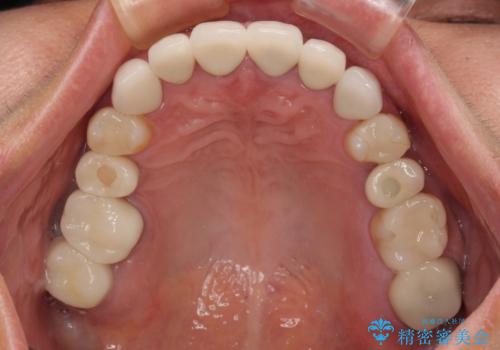

- 地元の歯科医院で治療を行っていたものの、難しいので都会に行くように指示をされたとのことで来院された患者様です。

右下のむし歯が歯肉縁下に及んでおり、歯周外科処置(歯冠長延長術)を行った上で、根管治療を行い、状態を整えて補綴治療を行うこととしました。

上顎前歯の根尖病変に痛みがありましたが、既に前歯が補綴治療済みであっため、外科的歯内療法(歯根端切除術)を行うことで解決することとしました。

新幹線で通院をされていたため、極力診療回数を減らして、一度にまとめて多くの処置を行うことで負担を軽減しました。